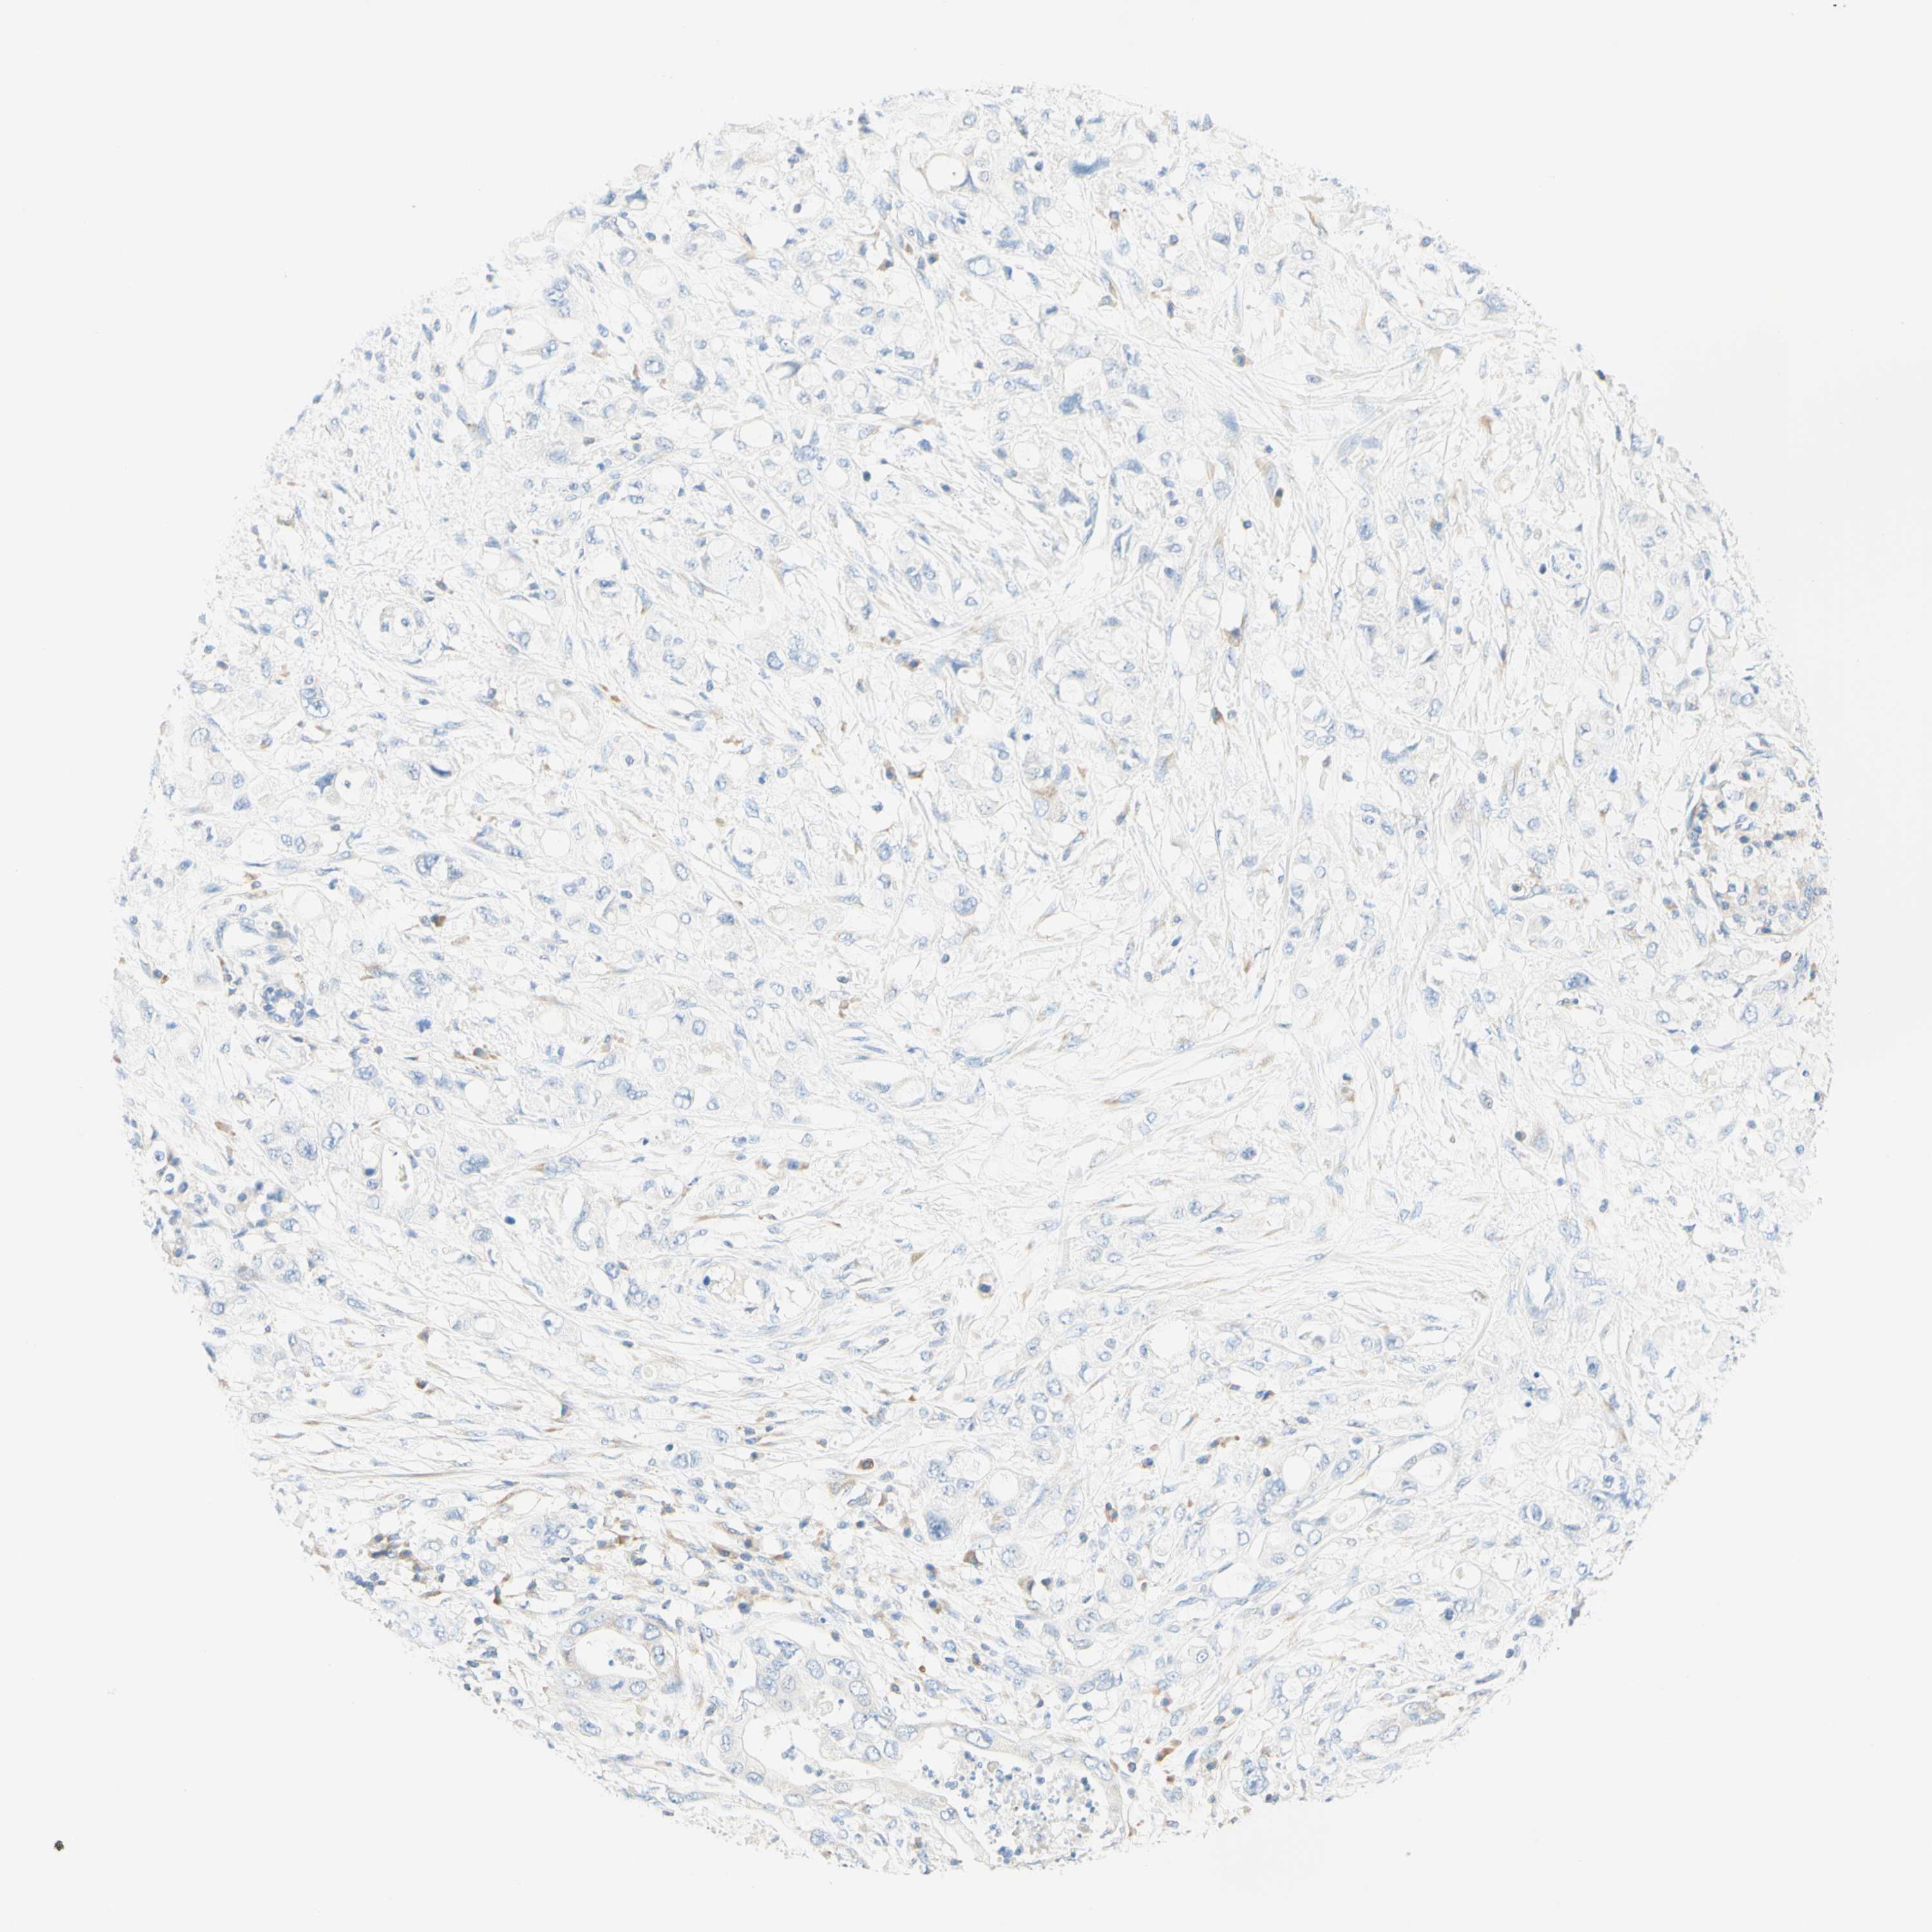

PANCREATIC CANCER - Protein expressioni

A mouse-over function shows sample information and annotation data. Click on an image to view it in a full screen mode. Samples can be filtered based on level of antibody staining by selecting one or several of the following categories: high, medium, low and not detected. The assay and annotation is described here.

Note that samples used for immunohistochemistry by the Human Protein Atlas do not correspond to samples in the TCGA dataset.

Antibody stainingi

Antibody staining in the annotated cell types in the current human tissue is reported as not detected, low, medium, or high, based on conventional immunohistochemistry profiling in selected tissues. This score is based on the combination of the staining intensity and fraction of stained cells.

Each image is clickable and will lead to virtual microscopy that enables deeper exploration of all samples and also displays staining intensity scores, fraction scores and subcellular localization as well as patient and tissue information for each sample.

Antibody HPA011157

Antibody CAB002223

Antibody CAB012978

Antibody CAB079960

Staining

High

Medium

Low

Not detected

Intensity

Strong

Moderate

Weak

Negative

Quantity

>75%

75%-25%

<25%

None

Location

Nuclear

Cytoplasmic/membranous

Cytoplasmic/membranous,nuclear

Adenocarcinoma, NOS

Adenocarcinoma, metastatic, NOS